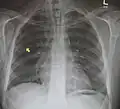

Pneumomediastinum is uncommon and occurs when air leaks into the mediastinum. The diagnosis can be confirmed via chest X-ray showing a radiolucent outline around the heart and mediastinum or via CT scanning of the thorax.

Pneumomediastinum and right sided pneumothorax post first rib fracture in a mountain biking accident. -

Pneumomediastinum with angel wing sign[15] - Pneumomediastinum as seen on ultrasound[16]